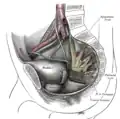

Les artères de la région fessière et fémorale postérieure. Coupe sagittale du bassin montrant le plexus sacré.

Coupe sagittale du bassin montrant le plexus sacré. Nerfs de la face postérieure du membre inférieur.

La face postérieure du muscle repose contre le sacrum. La face antérieure du muscle est liée au rectum (surtout du côté gauche du corps) et au plexus sacré[1].

Le muscle piriforme est innervé par le nerf du muscle piriforme, branche de division postérieure du plexus sacral (racines S1, S2)